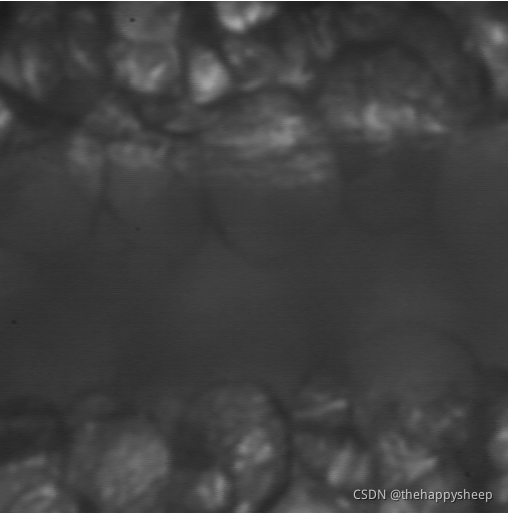

(1)原始图